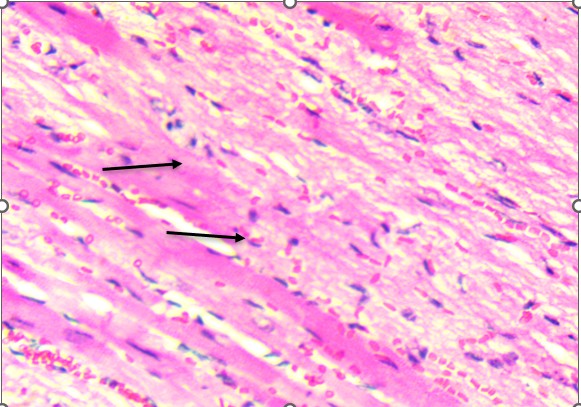

Histological analysis revealed that the heart was structurally preserved in all groups. In both control and treated animals, the cardiac tissue exhibited well-aligned myocardial fibers with distinct cross-striations and centrally located nuclei. No evidence of myocardial necrosis, interstitial edema, vascular congestion, or inflammatory infiltration was observed. Even in high-dose groups, the myocardium retained normal architecture, supporting the conclusion that the extract did not induce structural cardiotoxicity under these experimental conditions (Figure 2). In contrast, the lungs demonstrated a more apparent dose-dependent vulnerability to the extract. Control animals exhibited healthy pulmonary architecture, with well-expanded alveoli, thin interalveolar septa, and intact bronchiolar epithelium. These features were largely maintained in the low-dose group, although a few animals showed mild epithelial irregularities.

A. Control. . B. Treated

Figure 2. Heart of Swiss albino mice: (A) Control myocardium showing intact fibers with clear striations and central nuclei. (B) Treated myocardium displaying preserved architecture without necrosis, edema, or inflammatory infiltrates.

Histological examination of the heart revealed well-preserved myocardial architecture in both control and treated animals (Figure 2A–B). Myofibrils were regularly aligned, cross-striations were intact, and nuclei were centrally placed, findings consistent with the absence of cellular injury or inflammatory infiltration. Even at the highest extract dose, the myocardium exhibited no signs of necrosis, edema, or vascular compromise, indicating that D. stramonium did not induce structural cardiotoxicity under these experimental conditions. This aligns with clinical observations of Datura poisoning in humans, where tachycardia and arrhythmias are common yet typically reversible, reflecting autonomic dysregulation rather than direct myocardial damage (Krenzelok, 2010; Al Shaikh & Sablay, 2005).